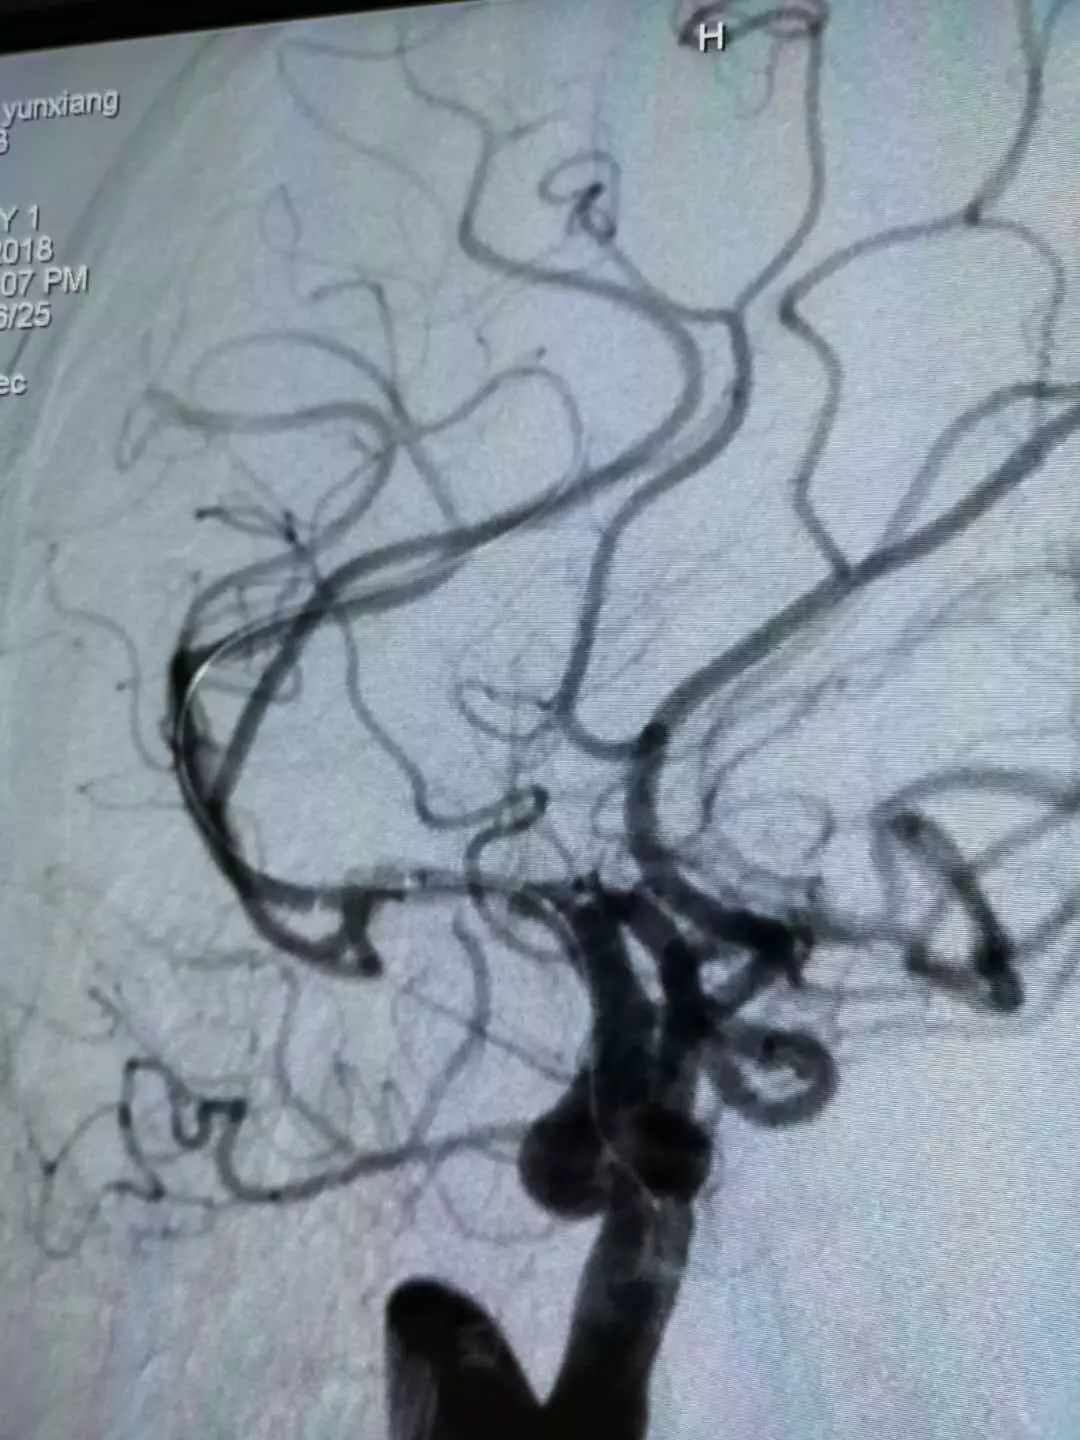

进行一次机械取栓

(Solitaire 4.0*20)

取栓后造影,发现为原位狭窄,调整为球囊扩张

球囊快速顺畅通过较迂曲的虹吸弯到达病变部位

(Neuro Rx 2.0*10)

球囊扩张4atm(Neuro Rx 2.0*10)

扩张后残余狭窄,且观察10min后再次闭塞

支架释放,扩张效果不佳(Enterprise 4.5x14)

同球囊导管再次支架内扩张6atm(Neuro Rx 2.0*10)

支架后扩张结果